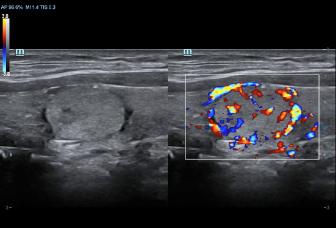

DC-70 Exp

–Ш–љ—Б—В—А—Г–Љ–µ–љ—В –і–ї—П –≤—Л—Б–Њ–Ї–Њ–Ї–∞—З–µ—Б—В–≤–µ–љ–љ–Њ–є –і–Є–∞–≥–љ–Њ—Б—В–Є–Ї–Є

X-Insight вАУ —Н—В–Њ –Њ—В–ї–Є—З–љ–Њ–µ —А–µ—И–µ–љ–Є–µ –і–ї—П –Њ–њ—А–µ–і–µ–ї–µ–љ–Є—П –љ–Њ–≤—Л—Е –≤–Њ–Ј–Љ–Њ–ґ–љ–Њ—Б—В–µ–є.

–°–Њ–≤–Љ–µ—Б—В–љ–Њ —Б —Б–Њ–≤—А–µ–Љ–µ–љ–љ—Л–Љ–Є —Г–ї—М—В—А–∞–Ј–≤—Г–Ї–Њ–≤—Л–Љ–Є —В–µ—Е–љ–Њ–ї–Њ–≥–Є—П–Љ–Є –љ–Њ–≤–Њ–µ —А–µ—И–µ–љ–Є–µ –Њ—В Mindray –њ—А–µ–Њ–±—А–∞–Ј—Г–µ—В –∞–Ї—В—Г–∞–ї—М–љ—Л–µ –Ј–∞–і–∞—З–Є –Ї–ї–Є–µ–љ—В–Њ–≤ –≤ –Ї–ї–Є–љ–Є—З–µ—Б–Ї–Є–µ –њ–Њ—В—А–µ–±–љ–Њ—Б—В–Є.

–°–Є—Б—В–µ–Љ–∞ DC-70 Exp —Б X-Insight –њ–Њ–Љ–Њ–≥–∞–µ—В —Г–њ—А–∞–≤–ї—П—В—М –њ–Њ–≤—Б–µ–і–љ–µ–≤–љ–Њ–є –Ї–ї–Є–љ–Є—З–µ—Б–Ї–Њ–є –њ—А–∞–Ї—В–Є–Ї–Њ–є —Б –ї–µ–≥–Ї–Њ—Б—В—М—О –Є —Г–≤–µ—А–µ–љ–љ–Њ—Б—В—М—О.

–Ю—Б–љ–Њ–≤—Л–≤–∞—П—Б—М –љ–∞ –≥–ї—Г–±–Њ–Ї–Њ–Љ –њ–Њ–љ–Є–Љ–∞–љ–Є–Є –њ–Њ—В—А–µ–±–љ–Њ—Б—В–µ–є –Ї–ї–Є–µ–љ—В–Њ–≤, –Ї–Њ–Љ–њ–∞–љ–Є—П Mindray —А–∞–Ј—А–∞–±–Њ—В–∞–ї–∞ —Б–Є—Б—В–µ–Љ—Г DC-70 Exp —Б X-Insight, —З—В–Њ–±—Л –Њ–±–µ—Б–њ–µ—З–Є—В—М eXpress Clarity, eXceptional Intelligence, eXceeding Experience.